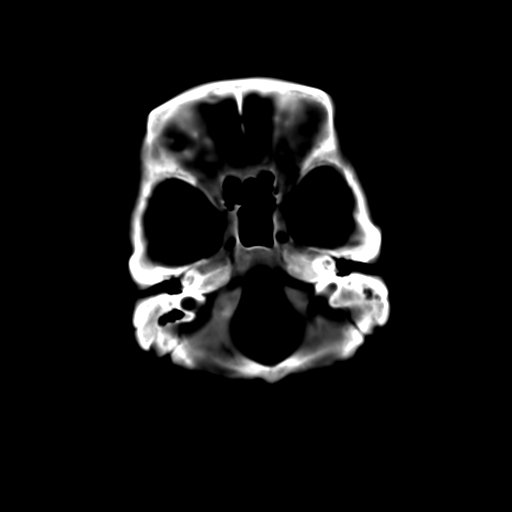

标题: CT23995:女,42岁,前额部外伤1小时,伤后头痛。 [打印本页]

女,42岁,前额部外伤1小时,伤后头痛。

颅内未见明显异常,枕骨松质骨瘤可能性大。颅骨板障起源骨瘤较常见,骨血管瘤有垂直骨针及粗大钙化,嗜酸性肉芽肿软组织有改变,典型者可见“纽扣状”死骨,年龄通常较小。

左枕骨松质骨不均匀低密度灶,边缘清楚,考虑良性松质骨性骨瘤可能性大。